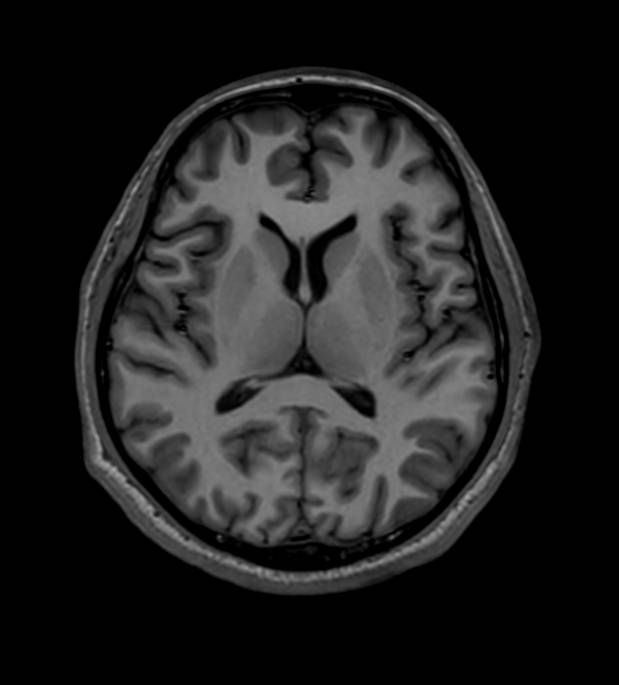

การลงทุนในเครื่อง MRI 3 Tesla ซึ่งใช้งบลงทุนมูลค่ากว่า 80 ล้านบาท ถือเป็นหนึ่งในแผนกลยุทธ์สำคัญของ BCH ในการเพิ่มศักยภาพโรงพยาบาลในเครือให้สามารถรองรับการรักษาโรคที่มีความซับซ้อน โดยเครื่องดังกล่าวมีความสามารถในการสร้างภาพวินิจฉัยที่มีความละเอียดสูง ช่วยให้แพทย์สามารถตรวจพบความผิดปกติได้ตั้งแต่ระยะเริ่มต้น โดยเฉพาะโรคทางสมอง ระบบประสาท หลอดเลือด และโรคกระดูกและข้อ ซึ่งช่วยเพิ่มโอกาสในการรักษาและลดภาระค่าใช้จ่ายด้านสุขภาพในระยะยาว

จุดเด่นของเครื่อง MRI 3 Tesla รุ่นใหม่นี้ ยังสามารถเพิ่มความเร็วในการตรวจวินิจฉัยได้ เร็วขึ้นเกือบ 2 เท่า เมื่อเทียบกับเทคโนโลยีมาตรฐาน ช่วยลดระยะเวลาการตรวจ เพิ่มความแม่นยำของผลวินิจฉัย และเพิ่มประสบการณ์ที่ดีให้กับผู้ป่วย ซึ่งสอดคล้องกับแนวโน้ม Healthcare Modernization ที่ให้ความสำคัญกับความรวดเร็วและประสิทธิภาพการรักษา